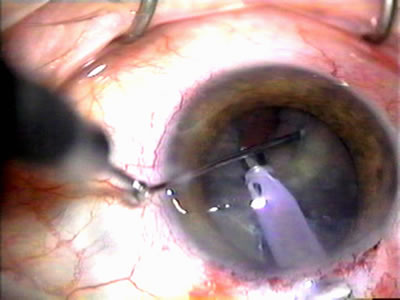

Fig. 1. The anatomic advantage of small incision cataract surgery for the glaucoma patient. A. Long-term bleb function with a large cataract incision is difficult to achieve with either ECCE-trabeculectomy or trabeculectomy followed later by ECCE. This bleb failed to form sufficiently when combined with large incision ECCE. The inflammation, bleeding, and long-term wound healing with stimulation of fibroblasts associated with this technique are more likely to cause bleb failure. In addition, the increased iris manipulation necessary to deliver the nucleus and subsequent iris repair adds to the long-term breakdown of the blood aqueous barrier. B and C. Two-site phacotrabeculectomy has the advantage of small incision cataract surgery combined with separate site trabeculectomy. The incision size is one third the size of the standard ECCE. The inflammation is less severe, and cataract wound healing is confined to the temporal area. Visual rehabilitation with phacoemulsification and foldable IOL is much faster. Phacoemulsification allows successful lens extraction even in the unfriendly environment of a smaller pupil compared with ECCE. The trabeculectomy is performed in an entirely different site, well away from the wound healing associated with temporal phacoemulsification. The likelihood of this filter functioning long-term is greater than with ECCE-trabeculectomy. D. The surgeon also has the option of single-site phacotrabeculectomy with foldable IOL. Both the lens extraction and trabeculectomy are performed through one small 3.5-mm limbal incision.

Fig. 7. Phacotrabeculectomy adjacent to a failed filter in cataractous eye. The ability to combine small-incision cataract extraction with trabeculectomy all through the same incision adjacent to the failed filter allows the surgeon to work in a familiar superior area. Avoiding incisions into the existing bleb decreases conjunctival buttonholes, hypotony, operating room time, and subconjunctival bleeding. A. Appearance of failed bleb with exposure of superior temporal quadrant gained with a corneal traction suture. B. Prepare a limbus-based conjunctival flap and a scleral flap. C. This bleb is at high risk to fail again justifying the need for MMC, 0.2 mg/cc applied on a pledget for 4 minutes. D. Insert the keratome and perform phacotrabeculectomy in the usual fashion.